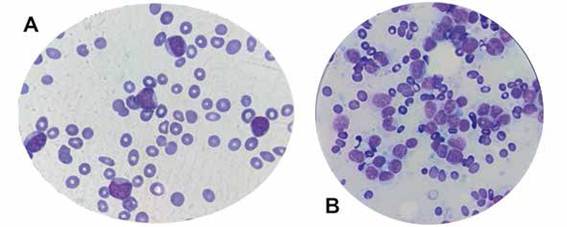

Paciente de sexo masculino de 57 años de edad, residente de Cochabamba, ocupación agricultor, con exposición a agroquímicos y, antecedente de Hipertensión arterial en tratamiento con enalapril. Referido a nuestra Unidad con diagnóstico de Linfoma NK luego de estudio de inmunohistoquímica (CD3-/CD56+). Cuadro clínico originado (1 mes anterior) por lesión dérmica pruriginosa hiperpigmentada a nivel de muslo derecho, región facial y tórax, caracterizada por un crecimiento progresivo y presencia de adenomegalia axilar e inguinal, asociada a síntomas B. Ingresó a Unidad de Emergencia en mal estado general, disneico con taquipnea requiriendo oxigenoterapia, taquicárdico (>106 lpm), febril (38,6 °C). (Figura 2). El Hemograma reportó Hb: 6.9 g/dL y Hct: 19 %, por lo que, se requirió transfusión de concentrado de Hematíes; leucocitos 53400/ul (S:3%, L:1%, M:3%, blastos linfoides 93 %), plaquetas 13000/uL. Asimismo, estudios de glicemia: 125 mg/dl, urea: 69 mg/dL, creatinina: 1,7 mg/dL, Ac. Úrico: 10,5 mg/dL, LDH: 1043 uL, serología viral VIH y hepatitis: negativos, citomegalovirus y Epstein Barr IgG: positivos. Se observó médula ósea hipercelular con infiltrado 90 % de linfoblastos (Figura 3). El paciente evolucionó desfavorablemente, compromiso hemodinámico, respiratorio y posterior compromiso vital.